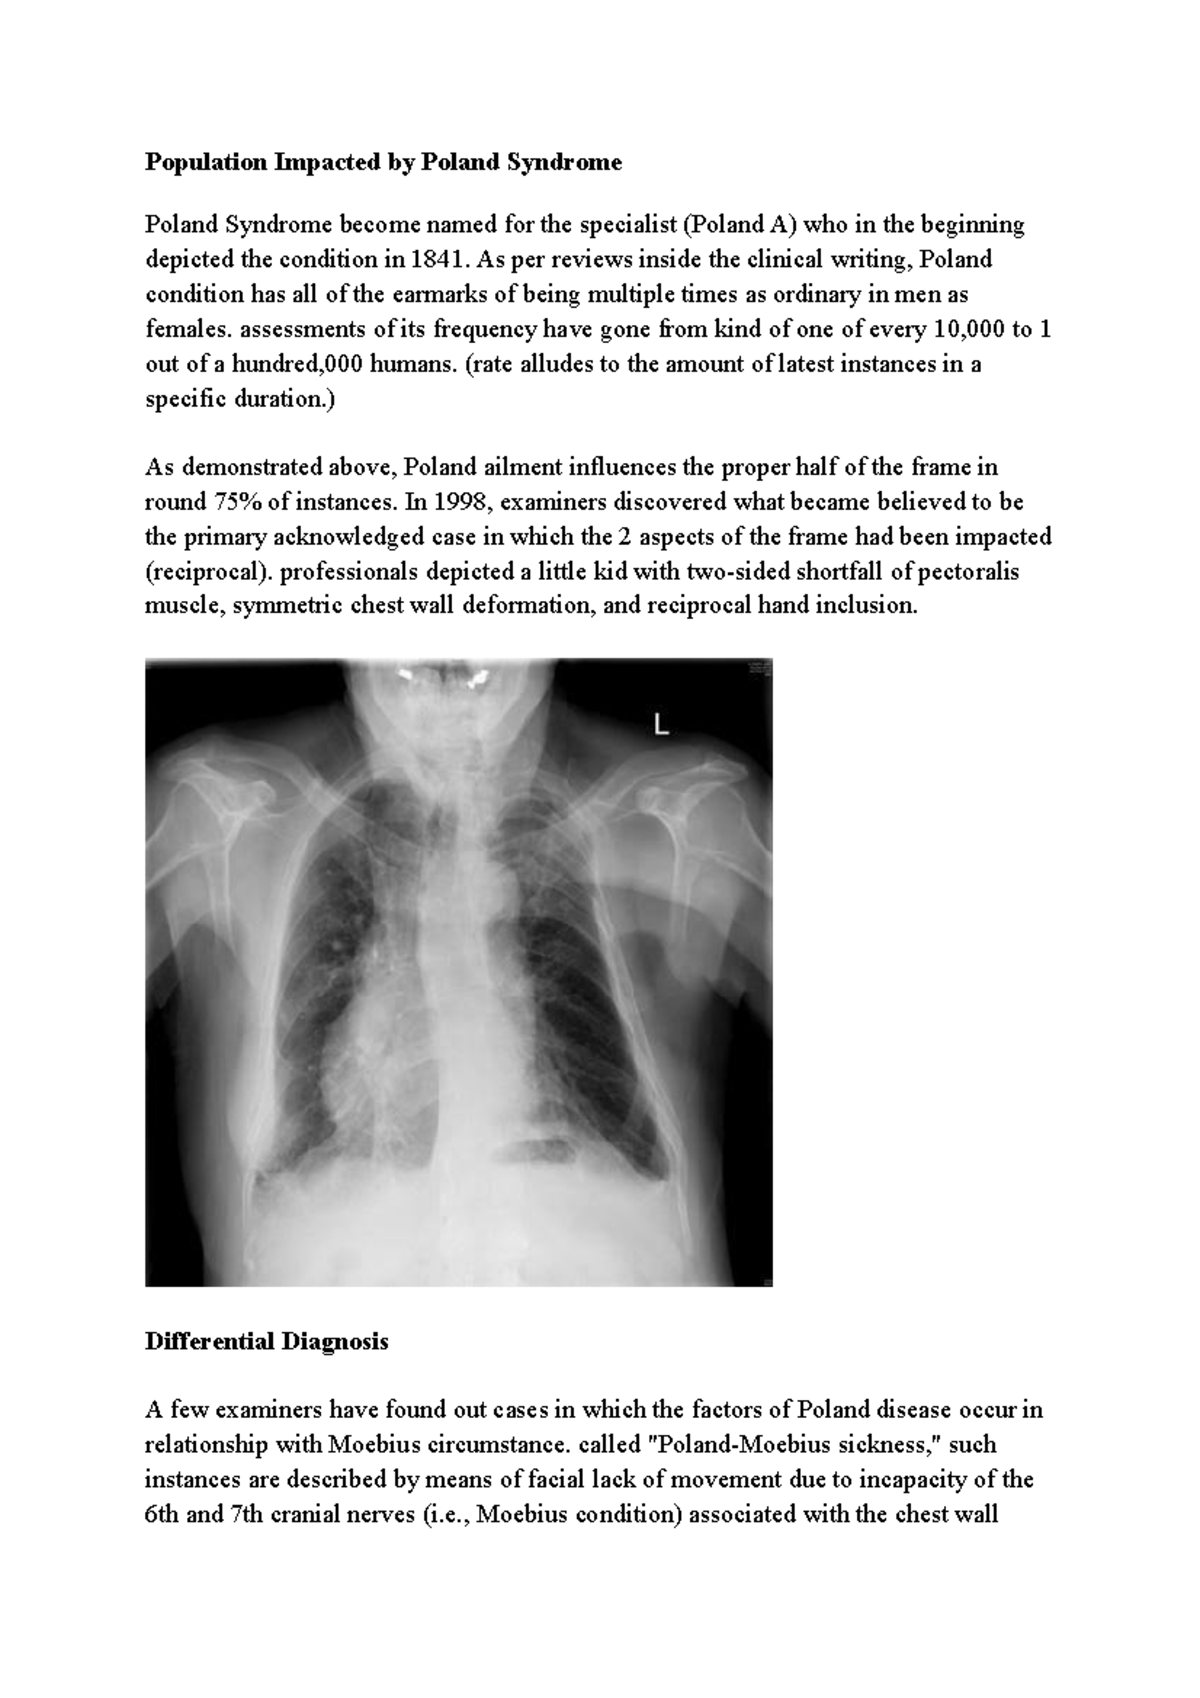

From radiologycases.my

Poland syndrome Radiology Cases Cost For Poland Syndrome Horton offers effective treatment for. It may also affect the ribs, breast, fingers, and shoulder blade. It will now be important to extend the discussion and the acceptability of our recommendations to a wider community of clinicians and families: Poland syndrome is a rare congenital condition that affects chest wall muscles and hand bones on one side of the body.. Cost For Poland Syndrome.